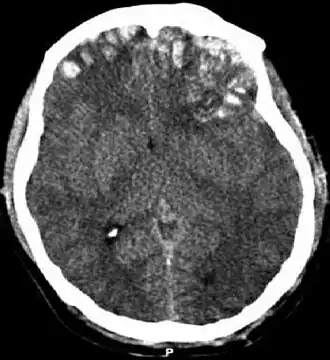

- Ушиб головного мозга: лёгкой, средней и тяжёлой степени (клинически). Ушиб головного мозга проявляется в ушибленной ране ткани мозга. Ушиб удар-противоудар наносится когда мозг ударяется о стенку черепа в месте непосредственного воздействия внешнего объекта на голову, получает одну ушибленную рану и затем ушибленная рана наносится на противоположную сторону мозга при резком замедлении движения ткани мозга. Клинические проявления зависят от расположения ушиба, и включают изменение психического состояния, повышенную сонливость, спутанность сознания, тревожное возбуждение. Небольшие интрапаренхиматозные кровоизлияния и припухлость окружающей ткани часто можно определить при компьютерной томографии.

При проникающих и тупых черепно-мозговых травмах чаще применяется бесконтрастная КТ. Она обладает достаточной чувствительностью для обнаружения острого кровотечения и переломов черепа. КТ также позволяет оценить серьёзность травмы по показателю увеличенного внутричерепного давления, отёка мозга, дислокации мозга. Об угрожающем характере травмы могут свидетельствовать следующие данные КТ: смещение срединной структуры, сглаживание борозды, увеличенные или сжатые желудочки, потеря нормальной дифференциации серого и белого вещества. Всем детям с нарушением сознания, с показателем по шкале комы Глазго ниже 14, с проникающей травмой, с фокальным неврологическим дефицитом должна быть немедленно проведена компьютерная томография. Для оценки неочевидных для показания к КТ случаев травмы головы у детей применяются критерии малого риска черепно-мозговой травмы.